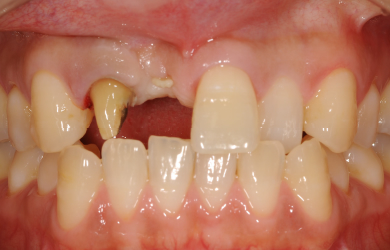

| 主訴 | 右上1番目の前歯を1週間位前に他の歯科医院で抜きました。右上2番目の前歯も高校生の時に神経を抜き被せものをしました。ブリッジにするかインプラントにするか迷っています。 | ||||||||||||||||||||||||||||||||

| 治療方針 | 抜歯した部分の骨が薄いため、そのままではインプラントを埋入出来ないため、GBR法と併用して、自分の骨を薄い部分に移植し、骨のボリュームを確保し、且つインプラント手術を同時に行うことにより、患者様にかかる外科的負担を軽減、治療期間を短縮する。 |

| 治療内容 | インプラント1本(GBR+自家骨移植)、メタルボンドセラミック2本 | ||||||||||||||||||||||||||||||||